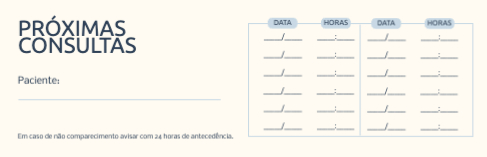

Escolher um template (Cartões de Visita com Dobra)

VoltarModelos de Cartões de Visita com Dobra

Explore diferentes estilos e modelos de cartões de visita com dobra. Escolha o design que melhor representa o seu negócio e personalize-o facilmente no nosso editor de design online.